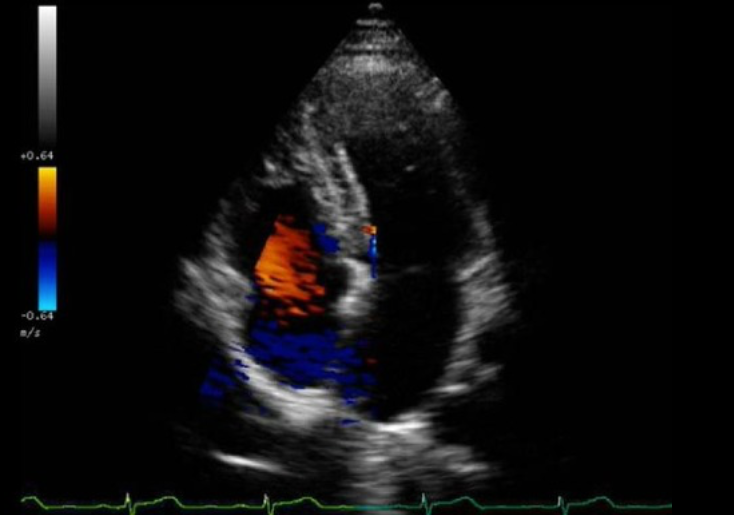

<p>What color Doppler artifact is demonstrated on the image?</p><p>a. cross talk <br>b. flash<br>c. mirror image<br>d. defocusing</p>

What color Doppler artifact is demonstrated on the image?

a. cross talk

b. flash

c. mirror image

d. defocusing

flash